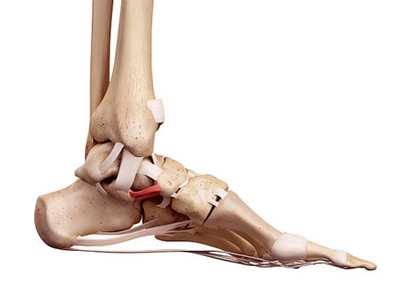

Стопа состоит из 28 костей и 34 суставов, из них 18 выпукло-вогнутые и 16 плоские. Все кости объединены в предплюсну, плюсну и пальцы. Кости предплюсны следующие: таранная, пяточная, кубовидная, ладьевидная, 1, 2, 3 клиновидные; кости плюсны: 1, 2, 3, 4 и 5. Все пять пальцев содержат 14 костей: у большого пальца имеется 2 фаланги, а у 2, 3, 4 и 5 пальцев — по 3 фаланги. Положение стопы в кинематической цепи нижней конечности связано с положением голени. Во время роста скелета вальгус стопы и низкий свод способствуют вторичному повороту бедра и коленного сустава во внутрь. После окончания роста высота свода и угол между большеберцовой и пяточной костями влияют на положение оси коленного сустава во фронтальной плоскости. Чем ниже свод стопы, тем больше ее вальгус, тем сильнее вальгус коленного сустава и тем сильнее наклонена голень во внутрь. Вальгус способствует пронации стопы, растяжению связок по внутренней поверхности коленного и голеностопного суставов, а также подошвенного апоневроза, что влияет на функцию всей нижней конечности.

Свод удерживается прыжковой связкой и подошвенной фасцией или подошвенным апоневрозом, который проходит через весь пролет арки. Подошвенный апоневроз расположен на подошвенной поверхности. Он является пассивным антагонистом трехглавой мышцы и проявляет свою функцию в зависимости от фазы ходьбы, которая связана с работой трехглавой мышцы голени. Апоневроз испытывает значительное растяжение, вызванное аксиальной нагрузкой и движением в плюсне-фаланговых суставах. Фасция представляет собой стабилизатор, функцией которого является затяжка арки и ее удержание. На подошвенной поверхности стопы расположены прыжковая связка. По сравнению с апоневрозом, прыжковая связка находится ближе к костям. Связка обладает низкими эластичными свойствами и препятствует смещению таранной кости.

• Передняя большеберцовая мышца выполняет ряд функций. 1. Стабилизация стопы во фронтальной плоскости. 2. Разгибание стопы, в результате чего таранная кость входит в вилку голеностопного сустава своей широкой частью. 3. Подъем медиального края стопы, уменьшение нагрузки на медиальные связки. 4. Препятствование подворачиванию стопы в ходьбе.

• Длинная малоберцовая мышц. 1. Разгибание стопы, благодаря чему таранная кость занимает в вилке более устойчивое положение. 2. Пронация стопы, подъем ее наружного края, что центрирует таран в вилке голеностопного сустава и способствует установке стопы на опору. 3. Стабилизация суставов предплюсны и 1 плюсневой кости, удержание пяточно-кубовидного сустава.

• Трехглавая мышца делает отталкивание стопы от опоры во время ходьбы. Сокращение мышцы вызывает компрессию пяточной и таранной костей, что стабилизирует подтаранный сустав и обеспечивает устойчивое положение заднего отдела стопы при контакте с опорой.